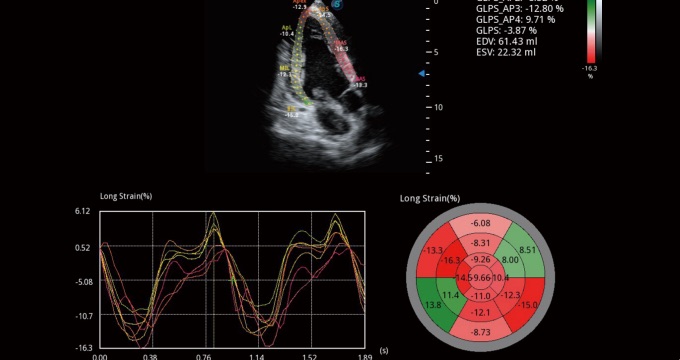

Single crystal transducers greatly improve signal ratio, acquire stunning images and provide superior sensitivity and resolution for both the near and far fields, by increasing the uniformity of crystal alignment and raising energy transmission efficiency. Single crystal C1-5 for abdominal and OB patients and S1-5 for cardiology and transcranial applications. Composite crystal linear transducers, by reforming the conventional piezoelectric materials, achieve a better acoustic spectrum and lower acoustic impedance to serve well in vascular, breast, thyroid, MSK, etc. The combo of 12L-A, 12L-B, 9L-A covers an ultra-wide frequency bandwidth, leaving nearly no blind spot for all sorts of scanning.